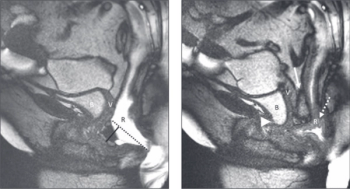

The report provides a universal set of recommendations and language for technique, interpretation and reporting of magnetic resonance defecography and is endorsed by six medical societies.